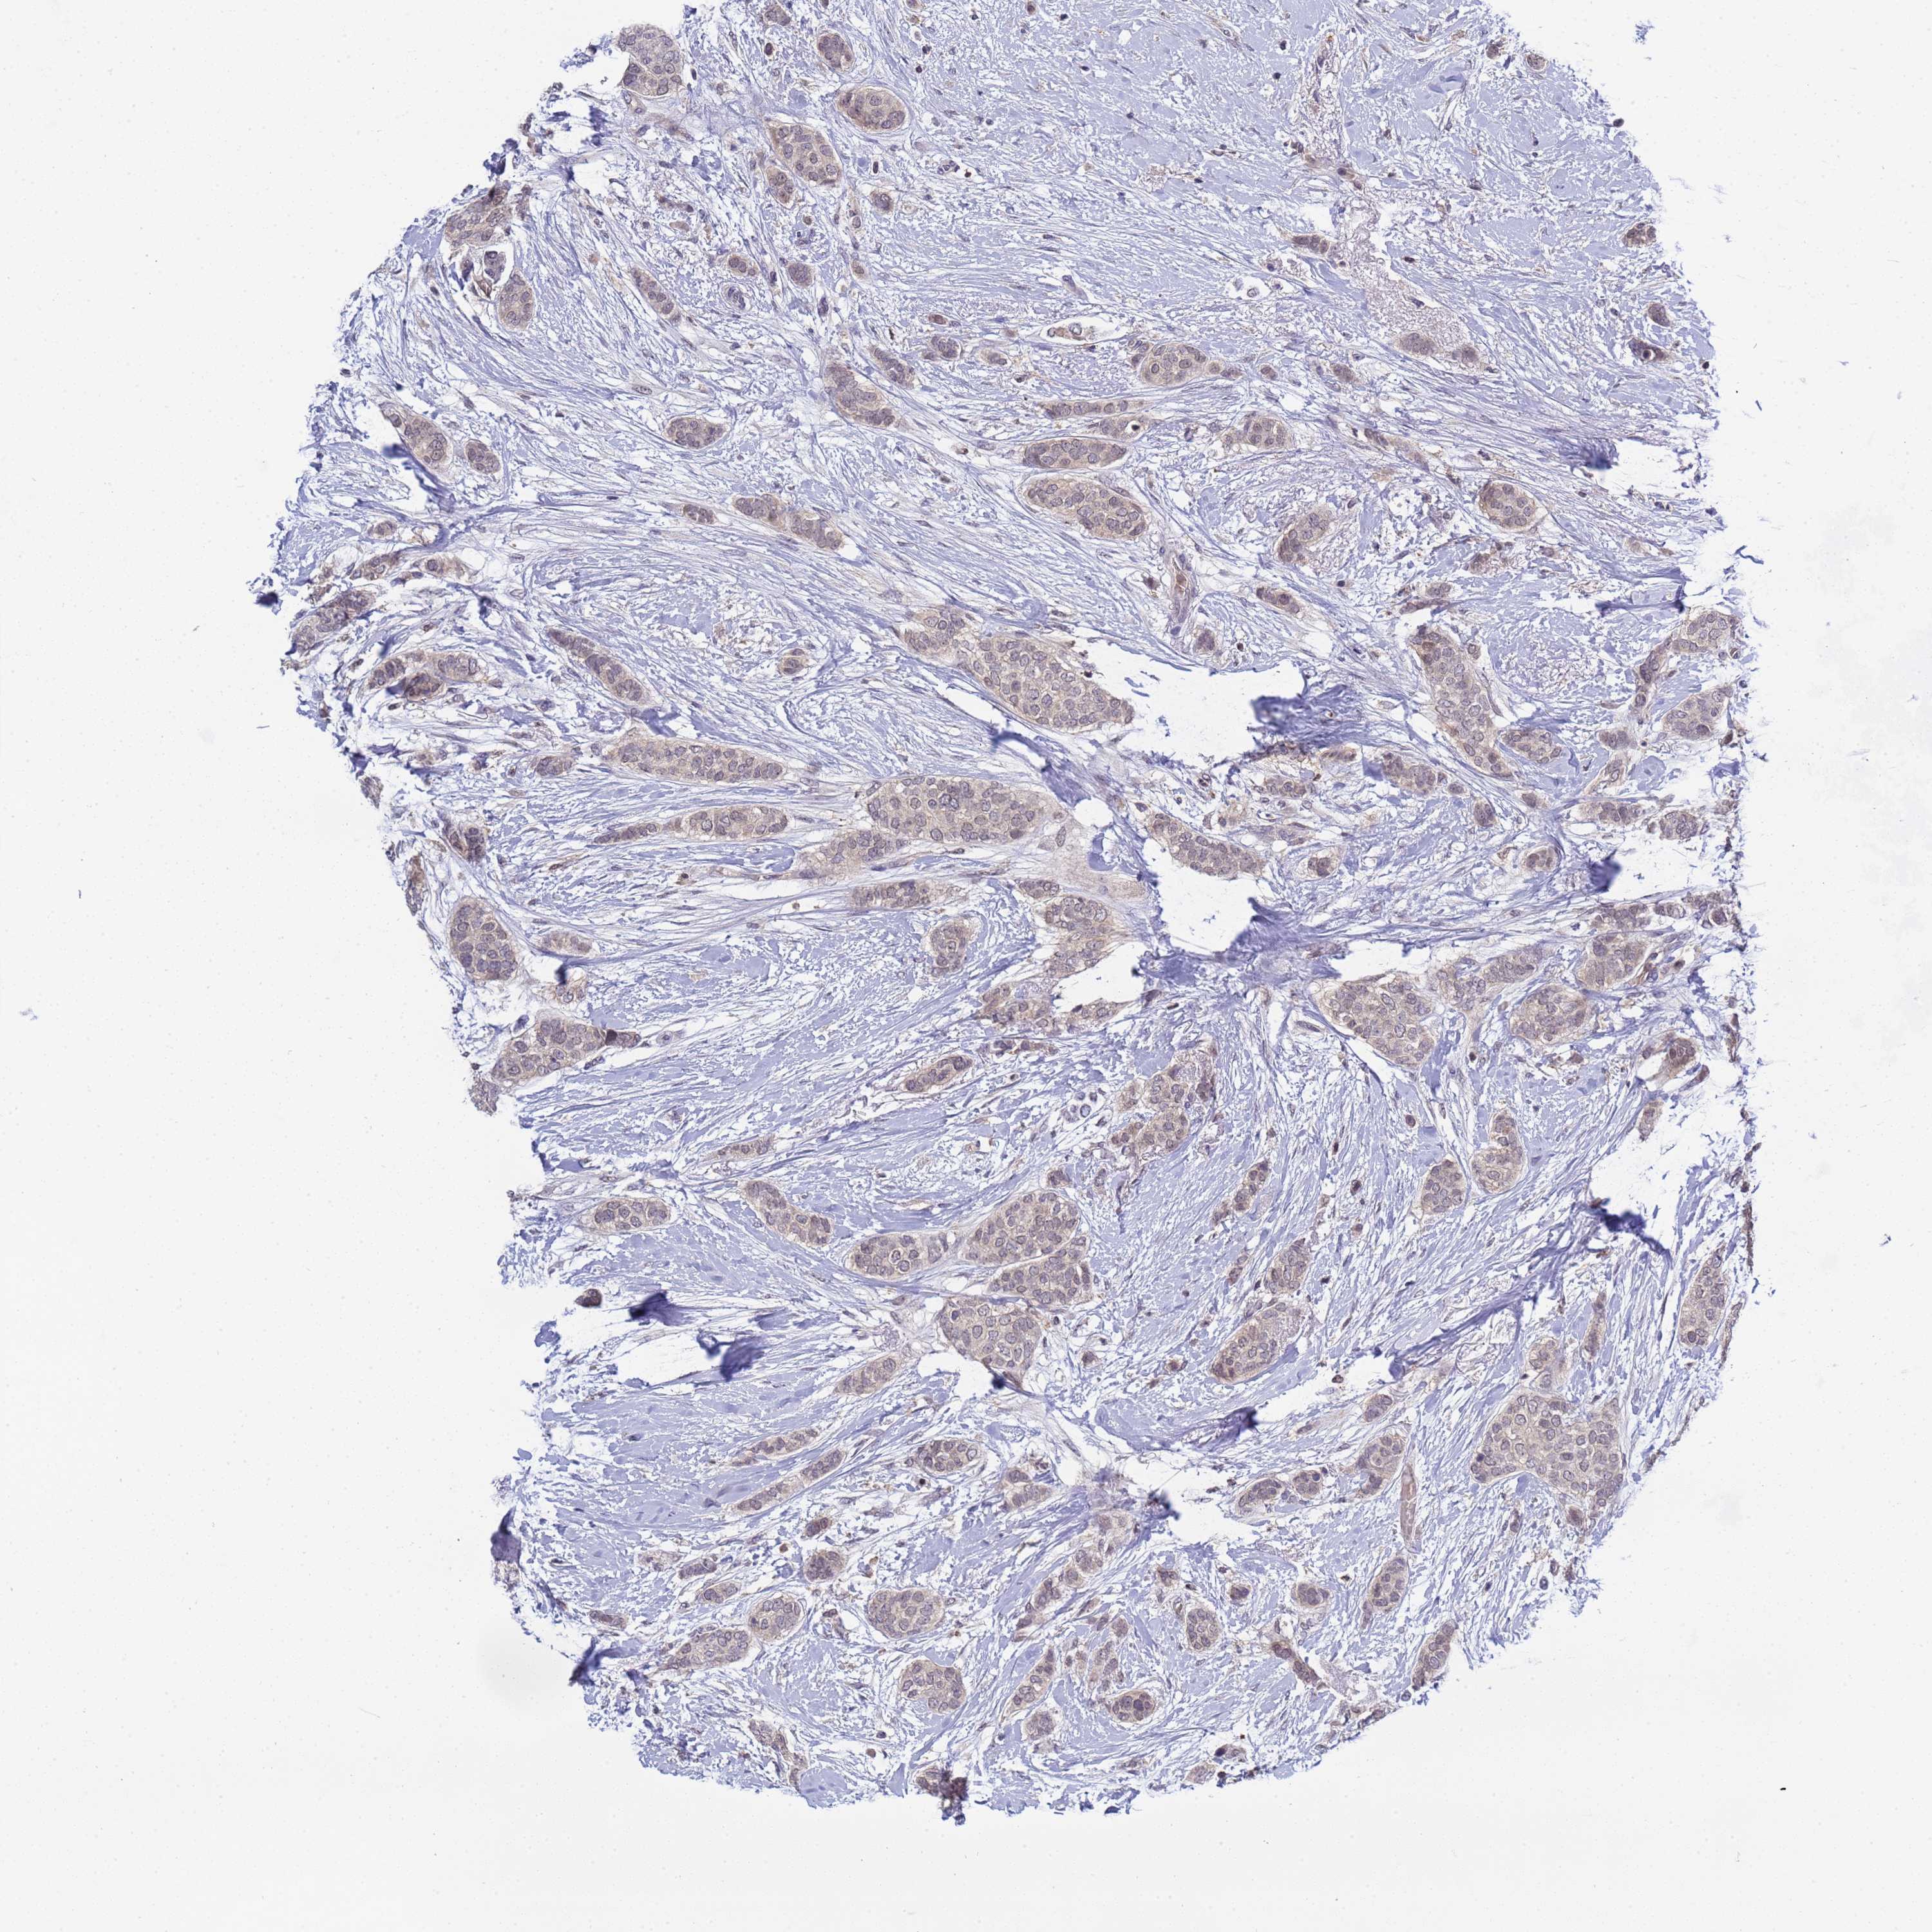

BRCA TCGA BRCA VALIDATION PROTEIN EXPRESSION

Breast cancer

Human cancer